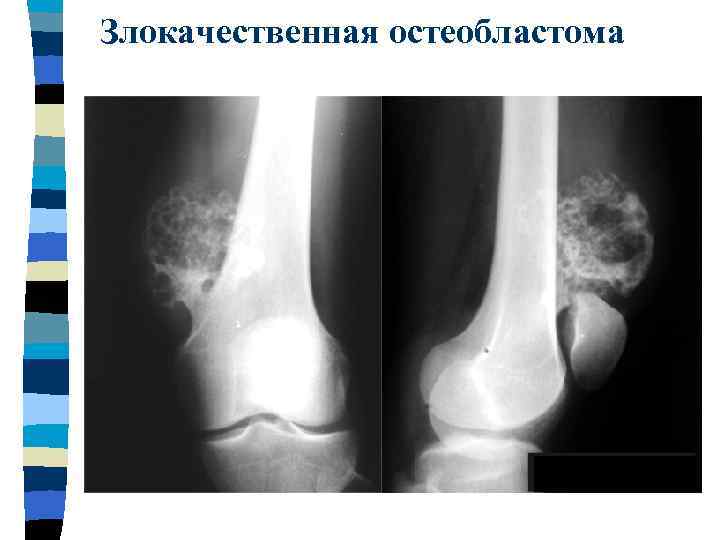

Злокачественная остеобластома